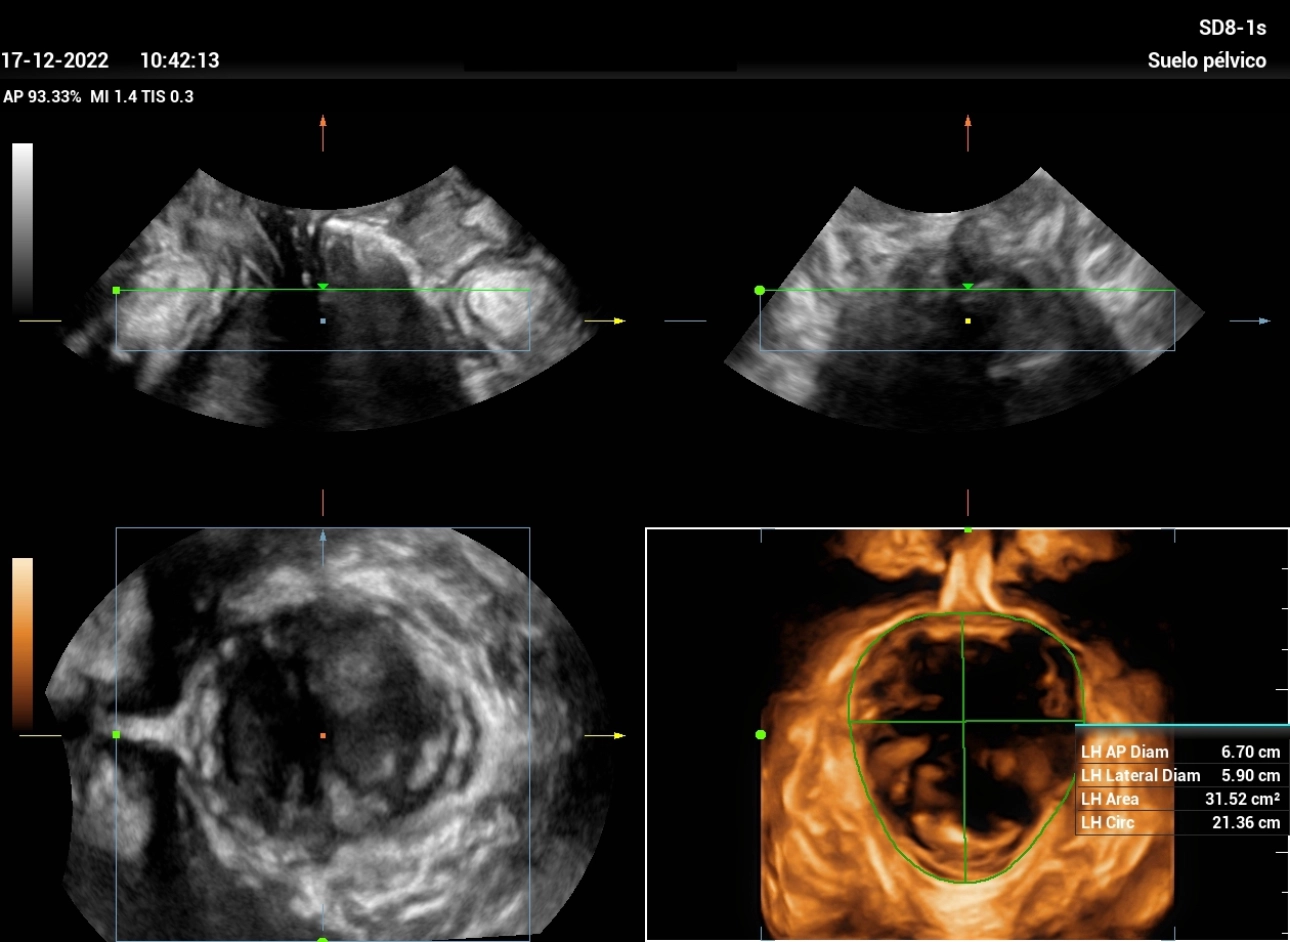

Ultrasound Journal 21 Ultrasound Evaluation of Stress Urine Stress Incontinence Ultrasound Stress urinary incontinence (sui), which refers to involuntary urine leakage due to physical exertion, sneezing or coughing, is the most common type. It helps in differentiating the various. Some people will still have urine. A test that measures the detrusor muscle pressure at rest and during activities like coughing and passing urine. Treatments for stress incontinence often can greatly reduce,. Stress Incontinence Ultrasound.

Ultrasound Journal 21 Ultrasound Evaluation of Stress Urine Stress Incontinence Ultrasound The minimum evaluation before primary midurethral sling surgery in women with symptoms of sui includes the following six. Stress urinary incontinence (sui), which refers to involuntary urine leakage due to physical exertion, sneezing or coughing, is the most common type. Stress urinary incontinence (sui) is the involuntary, sudden loss of urine secondary to increased intraabdominal pressure that is bothersome or. Stress Incontinence Ultrasound.

Ultrasound Journal 21 Ultrasound Evaluation of Stress Urine Stress Incontinence Ultrasound A test that measures the detrusor muscle pressure at rest and during activities like coughing and passing urine. Treatments for stress incontinence often can greatly reduce, and possibly stop, urine leakage. It helps in differentiating the various. Stress urinary incontinence (sui) is the involuntary, sudden loss of urine secondary to increased intraabdominal pressure that is bothersome or affecting the. Some. Stress Incontinence Ultrasound.